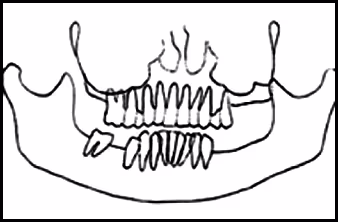

These figures demonstrate the visual effects on the image when the patient’s head is too far forward during exposure: spine superimposes over the ramus area, nasal fossa and maxillary sinus become clearly evident, and the anterior teeth are narrowed and blurred.

Figure 51A. Panoramic Image.

Figure 51B. Panoramic Schematic.